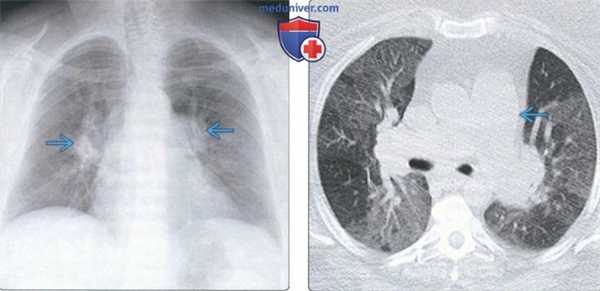

(Слева) На рентгенограмме органов грудной клетки в прямой проекции у пациента с легочной гипертензией, ассоциированной с приемом фенфлурамина в анамнезе, определяется выраженное расширение центральных легочных артерий.

(Справа) На аксиальной КТ без КУ у этого же пациента определяется расширение легочного ствола наряду с разбросанными «мозаичными» участками повышенной плотности легочной паренхимы. Фенфлурамин после 1997 года отсутствует на рынке из-за высокого уровня осложнений, преимущественно поражения клапанов сердца и легочной гипертензии.